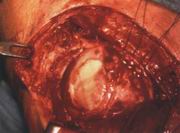

小切口显示肩袖破裂(图26)。

钳夹处为肩袖破裂口(图27)。